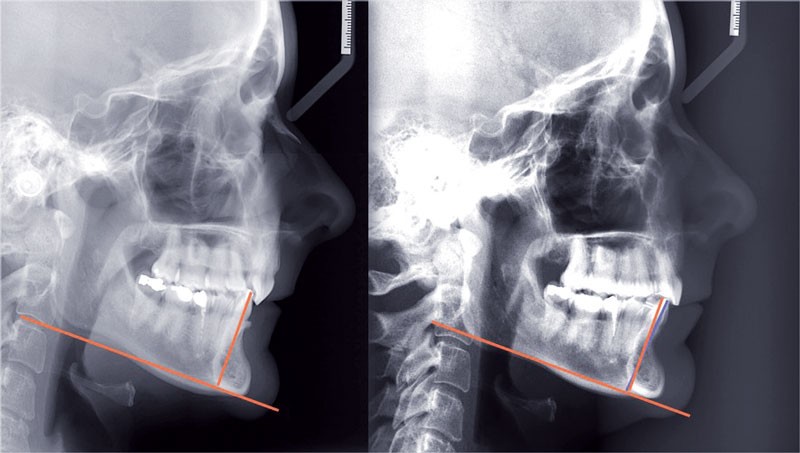

Un appareillage Damon métal a été mis en place, réalisé à partir d’un set up numérique Insignia pour obtenir un contrôle précis des torques et de la forme d’arcade et réduire le temps de finition grâce à un collage indirect très précis.

De larges surélévations postérieures étalées ont été mises en place et la patiente a porté des élastiques précoces suivant les principes de la technique Damon. Les 14 et 24 rempliront le rôle des 13 et 23.

Les objectifs de traitement ont été remplis. Nous avons observé un excellent contrôle du torque et une absence de perte de l’occlusion postérieure grâce à la technique Insignia.